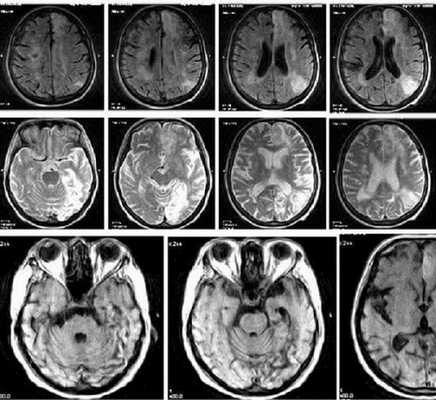

Красным выделен участок ишемии мозга в динамике на МРТ

МР-снимок показывает дистрофические изменения белого вещества вокруг желудочков мозга, характерные для хронической ишемии (лейкоареоз)

Ишемический инсульт (МР-сканирование)

Очаги ишемии головного мозга на МРТ

Нейровизуализационные методы: КТ, МРТ головного мозга, МР-ангиография (артерии и вены головного мозга ), при необходимости рентгеноконтрастная церебральная ангиография. Нейровизуализация позволяет исключить другие заболевания (опухоль, гидроцефалию) и подтвердить сосудистый характер нарушений. Предпочтительнее МРТ головного мозга, на которой выявляются характерные для хронической ишемии мозга изменения:

- лейкоареоз — изменение белого вещества вокруг желудочков головного мозга (на рисунке 1, белое свечение вокруг желудочков);

- лекоэнцефалопатия — поражение белого вещества головного мозга (на рисунке 1 и 3, светлые участки в подкорковом веществе);

- малые инфаркты, ишемические инсульты (рисунок 3);

- множественные микрокровоизлияния (рисунок 2 — темные участки);

- атрофия коры головного мозга.